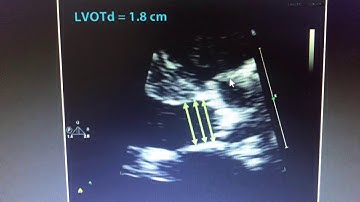

Hot Tips - Calculating the Aortic Valve Area Using the Continuity Equation